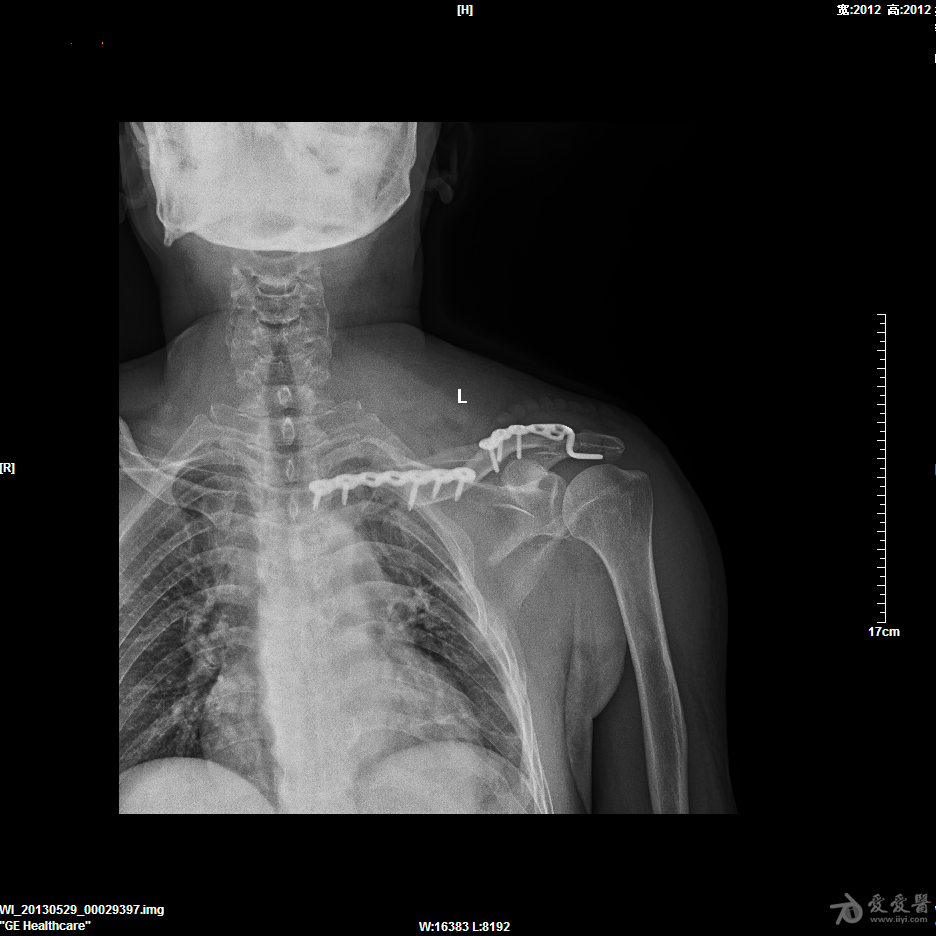

胫骨开放性骨折髓内针固定

57岁男性,骑摩托车摔伤,诊断1.右胫骨开放粉碎性骨折 2.腓骨粉碎性骨折 3.左锁骨粉碎性骨折(近、远端) 4.左肩胛骨粉碎性骨折 5.颅脑外伤。

入院后急诊清创缝合、右跟骨牵引,第9天,颅脑外伤稳定后行手术治疗。

这是术后片,术前片随后奉上。

楼主的手术观点可行,只是手术技巧还需进一步提高。1肩部的骨折应是一个浮肩损伤,片上隐约可以看到肩胛颈部的骨折,需要进行悬吊复合体完整性的恢复,或许肩胛骨进行固定效果会更理想。2腓骨骨折涉及到胫腓联合上8CM以内,所以需要固定,但胫腓骨的固定顺序错误,应先固定腓骨。如果术前或术中可以证实胫腓间韧带完整,腓骨的近端骨折可以不固定。3,aap髓钉提供立体的远端锁定,可以选择前后向先置钉。4像这样的带楔形骨块的简单骨折,易造成成骨不良,我更愿意选择双骨双钢板固定。